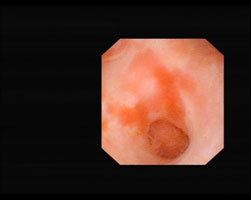

![]() Flächiger Nierenbeckenkrebs |